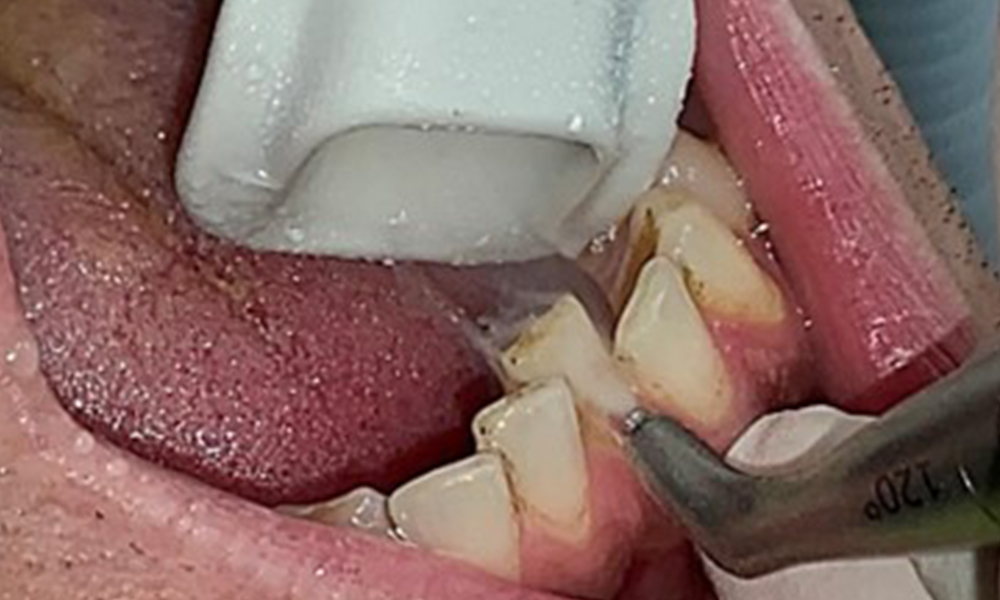

The patient has full dentition with a total of 28 teeth. There were noteworthy erosions and attritions. (Fig. 4, Fig. 5). Due to bruxism, the patient has been wearing a splint with an adjusted bite block at night for many years. The erosions were caused by long-term consumption of isotonic beverages. No periodontal bone loss or active caries were observed.

Fig. 5: Close-up view of teeth 45 to 47. The green arrows show dental attrition and erosions of the buccal cusps with partial enamel loss, © Dr R. Krapf

Full complement of adult teeth with no caries or radiologically recognizable bone loss was observed (Fig. 6). Radiological enamel and cusp loss were particularly evident on 36 and 37.